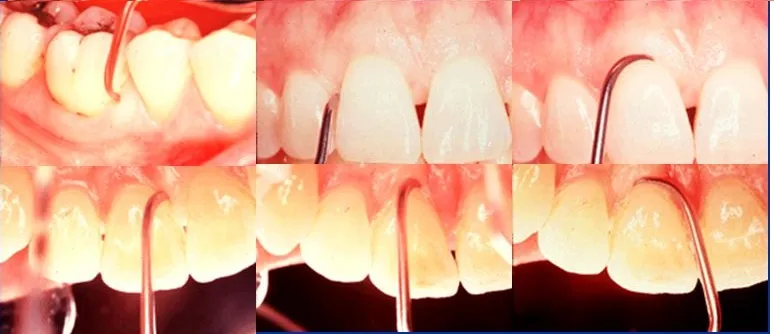

Gracey 9-10 Posterior teeth – for buccal and lingual surfaces of molars using the horizontal technique:

- The Gracey 9/10 is predominantly used on the buccal and lingual molar aspects, especially around the bifurcation, where access can be difficult. Its wide contra-angle, wide return angle, and short shank make it a distinctive instrument. The toe is very nearly in line with the instrument handle, making this pattern especially suited to the least accessible root surfaces, while still allowing good control